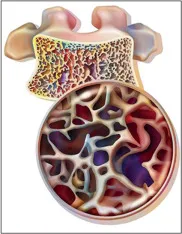

DRPAD além do Tolvaptana: Novas Perspectivas Terapêuticas nas Diretrizes KDIGO 2025

Além do tolvaptana, as diretrizes KDIGO destacam a importância de medidas não farmacológicas e abordagens complementares no manejo da DRPAD, como controle rigoroso da pressão arterial, redução de ingesta de sal e aumento de ingestão hídrica. Estudos em andamento também avaliam terapias-alvo envolvendo vias do mTOR, cAMP e inflamação. O manejo multidisciplinar permanece essencial para retardar a progressão da doença e melhorar a qualidade de vida.